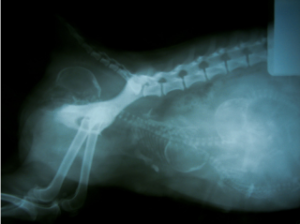

Leishmaniasis visceral

¿Qué es la leishmaniasis visceral canina? La leishmaniasis visceral canina es una enfermedad grave de los perros producida por un...